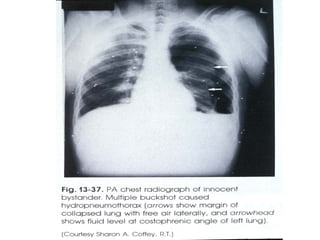

If outside air entered the space between the pleural membranes (pleural space) the elastic lung tissue would collapse inward and the chest wall would expand outward.

Outside air between the pleural membranes  (pneumothorax) allows the elastic lung to collapse inward and the chest wall to expand outward.  The pleural cavity becomes obvious.  Once the lung is collapsed, the person has only the one lung to survive on.

Outside air betweenthe pleural membranes (pneumothorax) allows the elastic lung to collapse inward and the chest wall to expand outward. The pleural cavity becomes obvious. Once the lung is collapsed, the person has only the one lung to survive on.